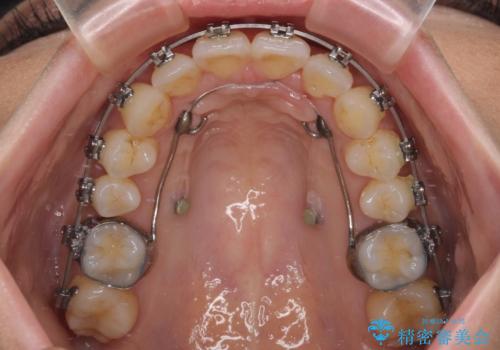

アンカースクリューと補助装置を使用して上顎大臼歯を遠心移動させることで咬み合わせを改善し、ワイヤー装置によりデコボコを解消しながら口元の突出感も改善していくこととしました。

出っ歯になることなく、上下前歯が綺麗に接触する状態で仕上げることができました。